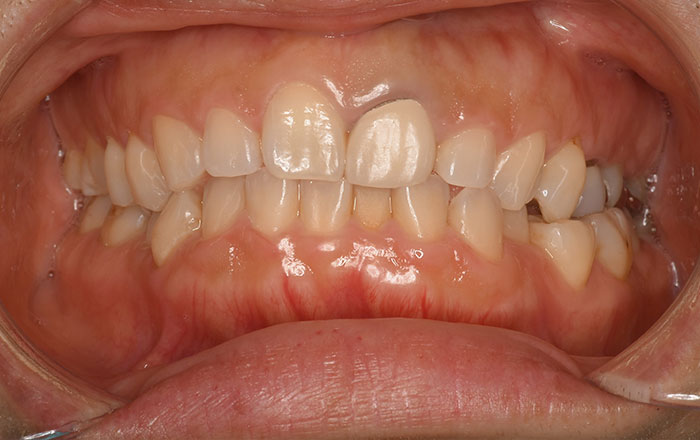

エアフロー(保険適用)

スイス・EMS社製のクリーニング機器で、安全性の高いアミノ酸パウダーを歯に吹き付けることにより、虫歯の原因となる歯垢を痛みなく取り除きます。